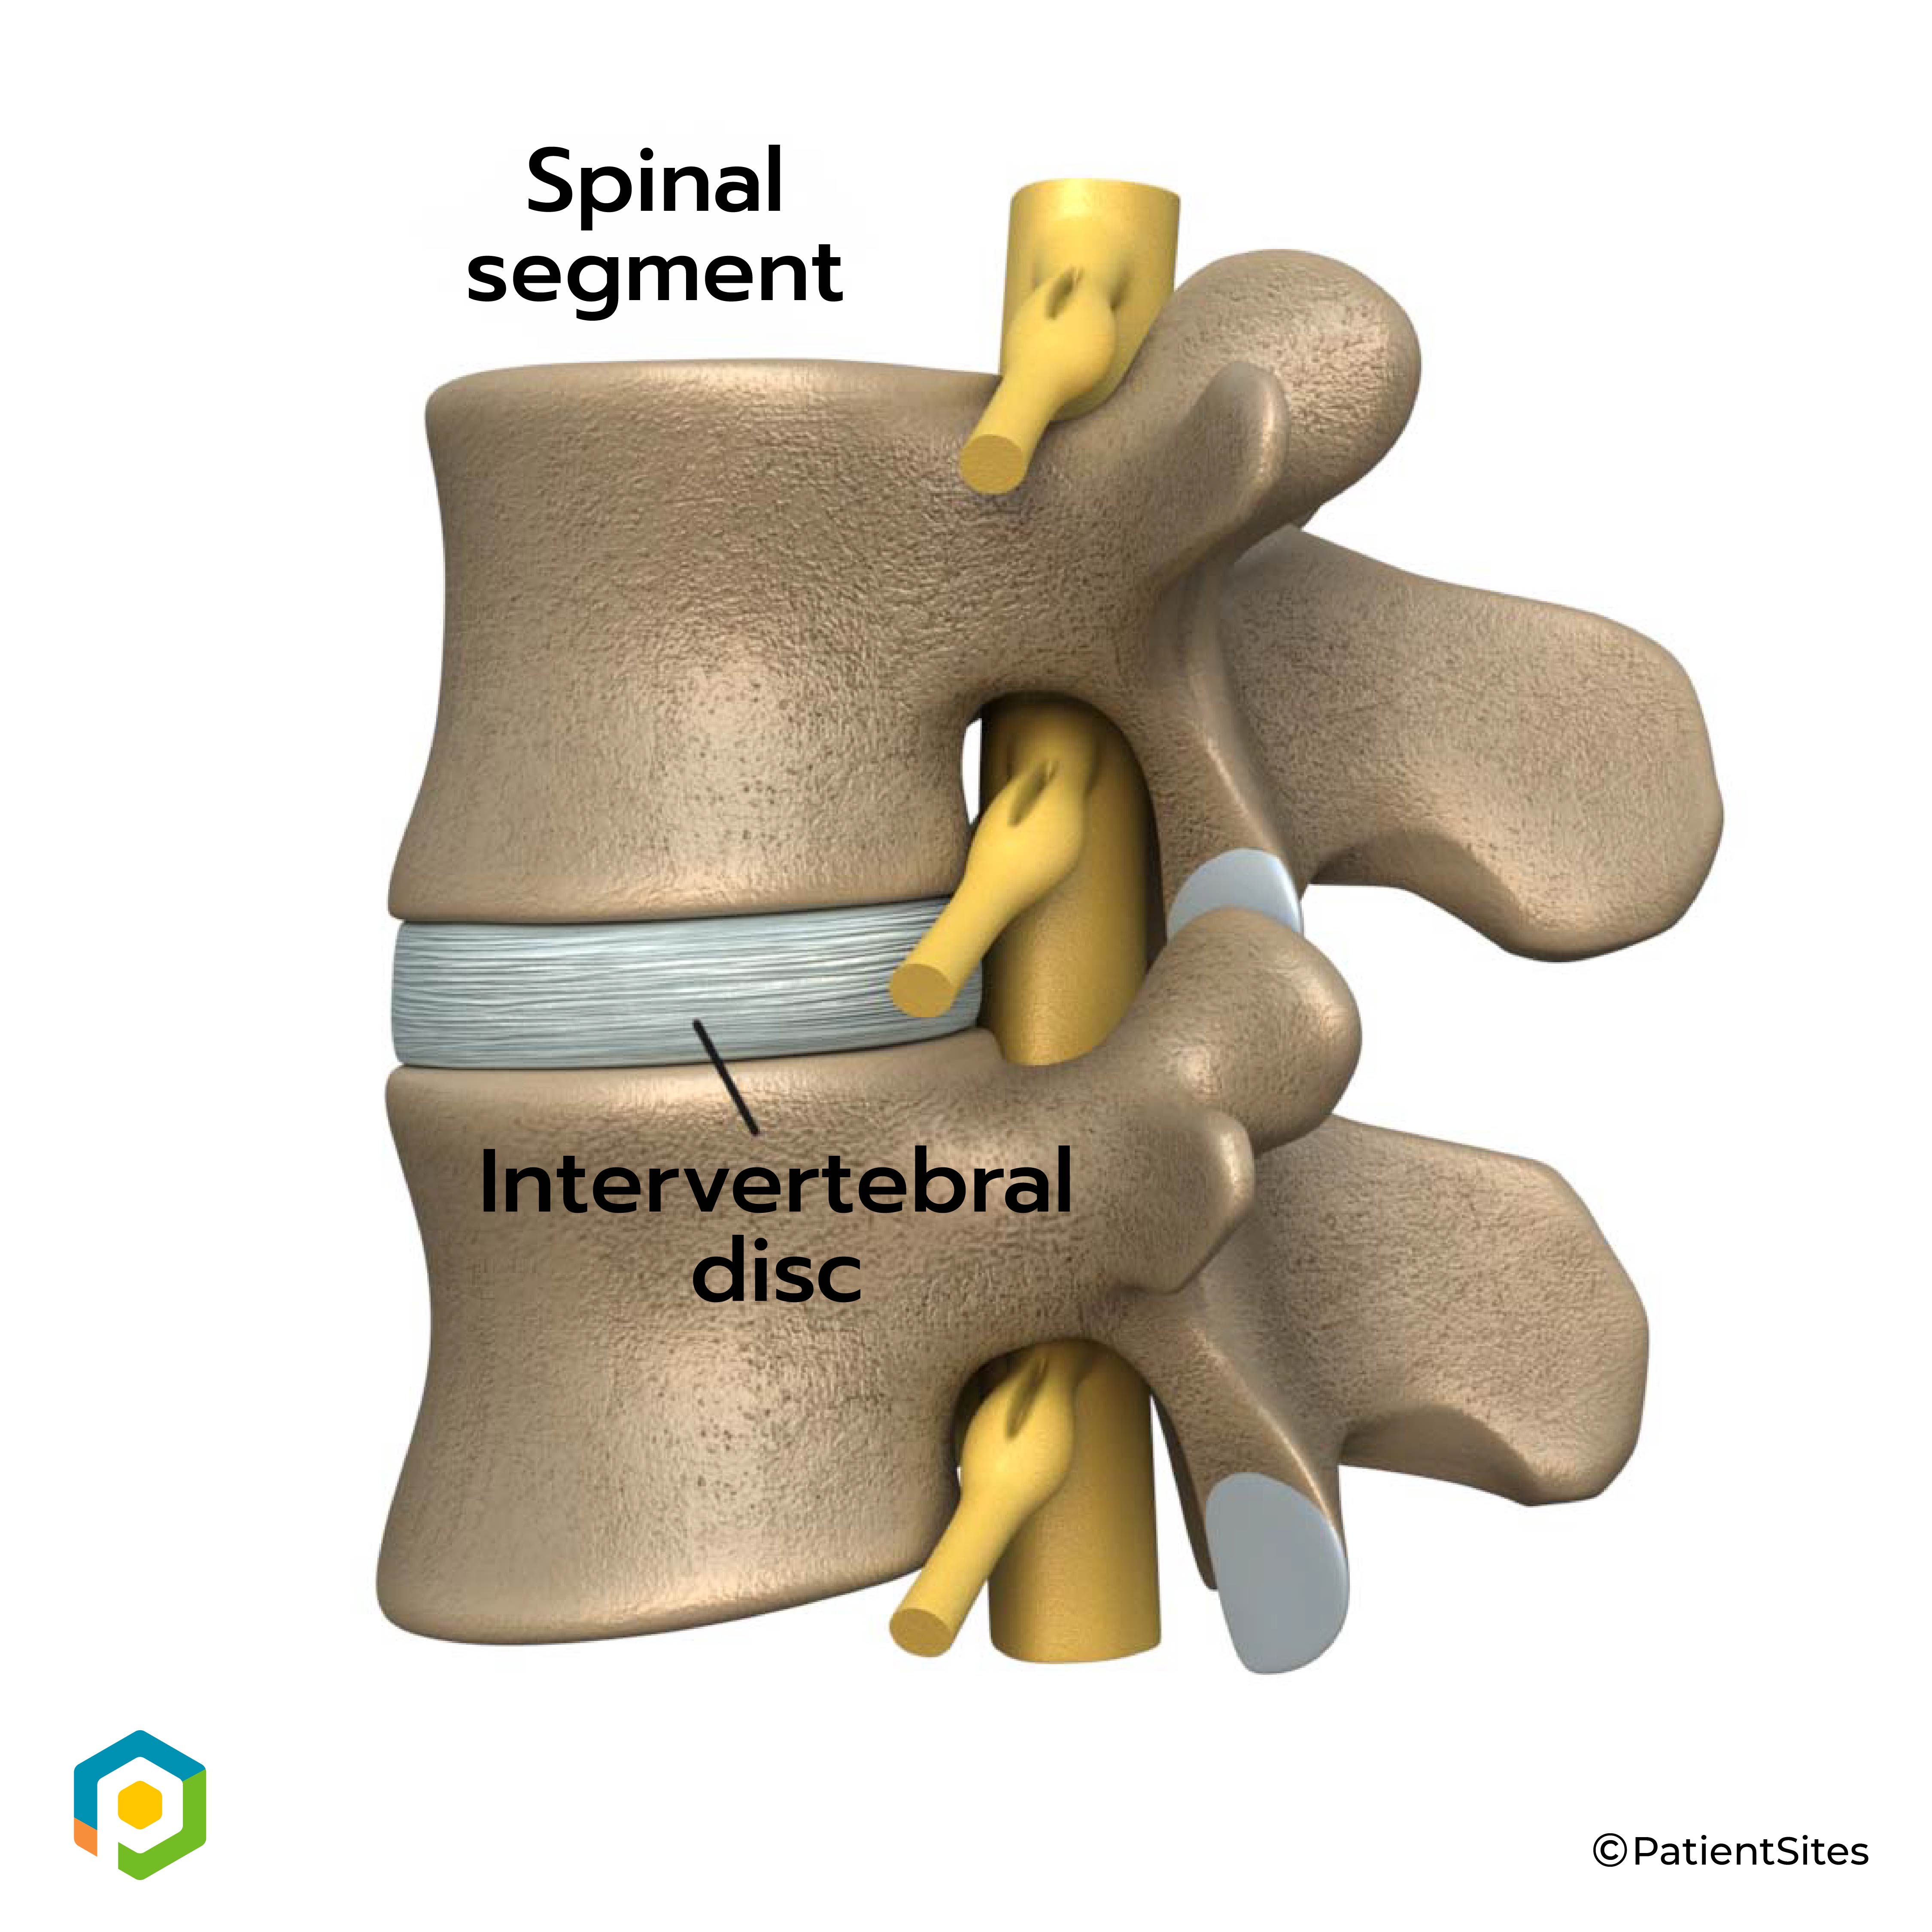

An intervertebral disc sits between each pair of vertebrae. The intervertebral disc is made of connective tissue. Connective tissue is the material that holds the living cells of the body together. Most connective tissue is made of fibers of a material called collagen. These fibers help the disc withstand tension and pressure.

Intervertebral Disc

The disc normally works like a shock absorber. It protects the spine against the daily pull of gravity. It also protects the spine during strenuous activities that put strong force on the spine, such as jumping, running, and lifting.